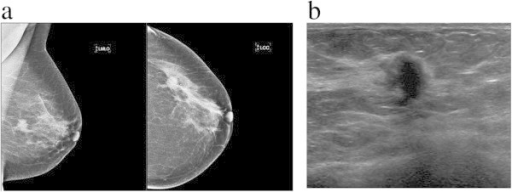

Lump or thickening

Lumps or thickened tissue can occur anywhere in the breast, including up to the collarbone and in the axilla. Breast lumps can present differently in different patients, e.g. they may be hard, soft, painless, painful, fixated, mobile, near the skin’s surface or deep in the breast tissue. A lump can also present as a thickened area of breast tissue that feels different from the rest of the breast.